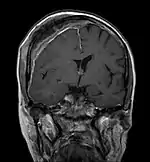

Scanner d'une métastase ostéocondensante dans l'os du crâne d'un patient souffrant d'un carcinome de la prostate. On reconnaît clairement l'extension de la métastase au-delà des limites initiales de l’os.

Par comparaison, scanner de métastases ostéolytiques dans l'os du crâne d'une patiente souffrant d'un cancer du sein. On distingue une ostéolyse plus grande sur le front, et plusieurs plus petites.